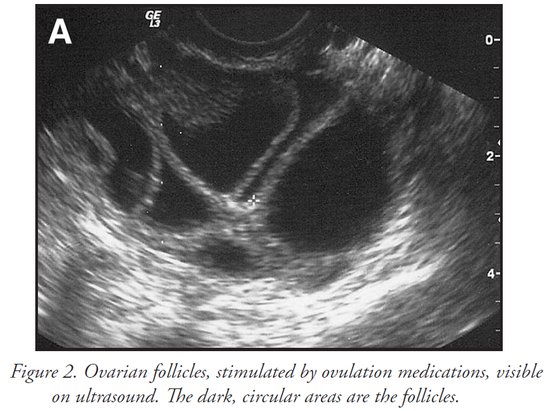

通过超声波监测和对血液中激素水平的测量,可以了解卵子的发育情况,一般来说要8-14天,卵泡达到一定的大小,就可以准备取卵了。

下图里黑色的区域就是药物刺激发育了的卵泡。